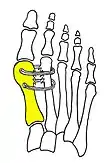

Syndesmosis procedure addresses specifically the two fundamental problems of metatarsus primus varus deformity that gives rise to the bunion deformity. They are leaning and instability of the first metatarsal bone . Syndesmosis procedure uprights the leaning first metatarsal bone with strong binding sutures between it and the second metatarsal bone (Fig. 2) and then also stabilizes it uniquely by creating a fibrous connecting bridge between these two bones (Fig. 3, 4). First metatarsal bone can be readily realigned because by definition of the metatarsus primus varus deformity its first metatarsal is abnormally loose and mobile.